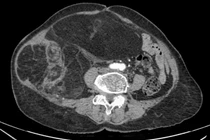

Sau quá trình khám lâm sàng, tìm hiểu diễn biến bệnh, thực hiện nội soi và siêu âm nội soi, các bác sĩ kết luận người bệnh có u mỡ thực quản dưới niêm mạc, kích thước 16 x 3,5 x 3 cm, đây là khối u có kích thước khủng, thông thường các khối u dưới niêm mạc đường tiêu hóa có kích thước thường nhỏ hơn 3cm.

u-mo-thuc-quan-1.jpg

Hình ảnh khu mỡ khủng trong thực quản dưới niêm mạc trên phim chụp - Ảnh BVCC